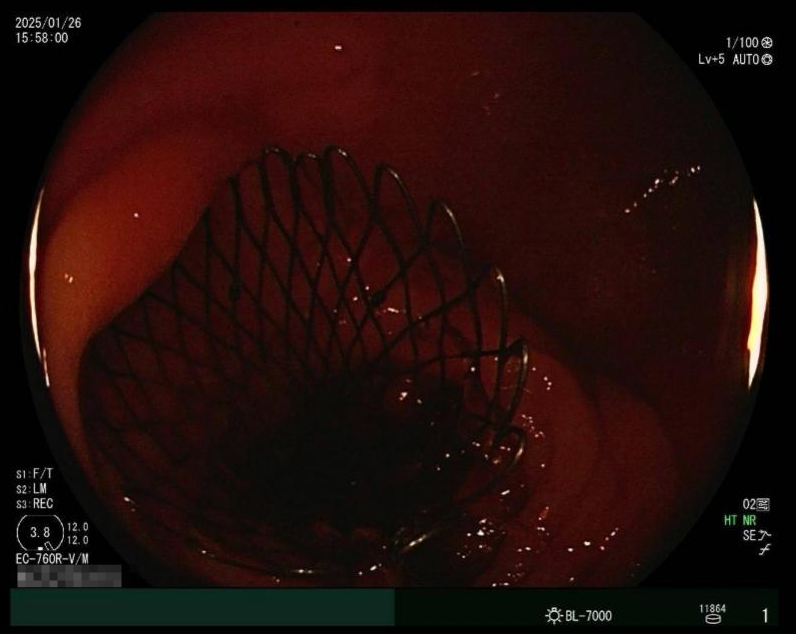

彼時正值除夕前夕,時間緊迫,王志斌主任迅速聯(lián)系北京中醫(yī)藥大學(xué)東方醫(yī)院方莊院區(qū)脾胃肝膽科王林恒主任,協(xié)調(diào)手術(shù)相關(guān)事宜。在兩個院區(qū)的緊密配合下,患者當(dāng)日下午順利轉(zhuǎn)入方莊院區(qū)內(nèi)鏡中心。在內(nèi)鏡室,脾胃肝膽科團隊?wèi){借過硬的專業(yè)技術(shù)和豐富的臨床經(jīng)驗,有條不紊地進行操作,并順利完成并開啟生命綠色通道——腸道支架介入手術(shù)。

治療前腹CT示腸腔明顯擴張 治療后立位腹平片示腸道梗阻較前明顯緩解